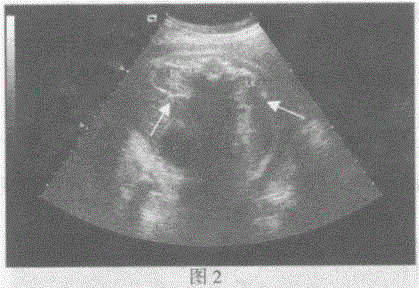

问题 临床资料:女,33岁,孕35周,常规超声检查。 超声综合描述:图1、图2箭头所指是胎儿哪一部位: 超声提示:

选项 A.胎儿肠管 B.胎儿脊柱 C.胎儿肾脏 D.胎儿心脏

答案 C